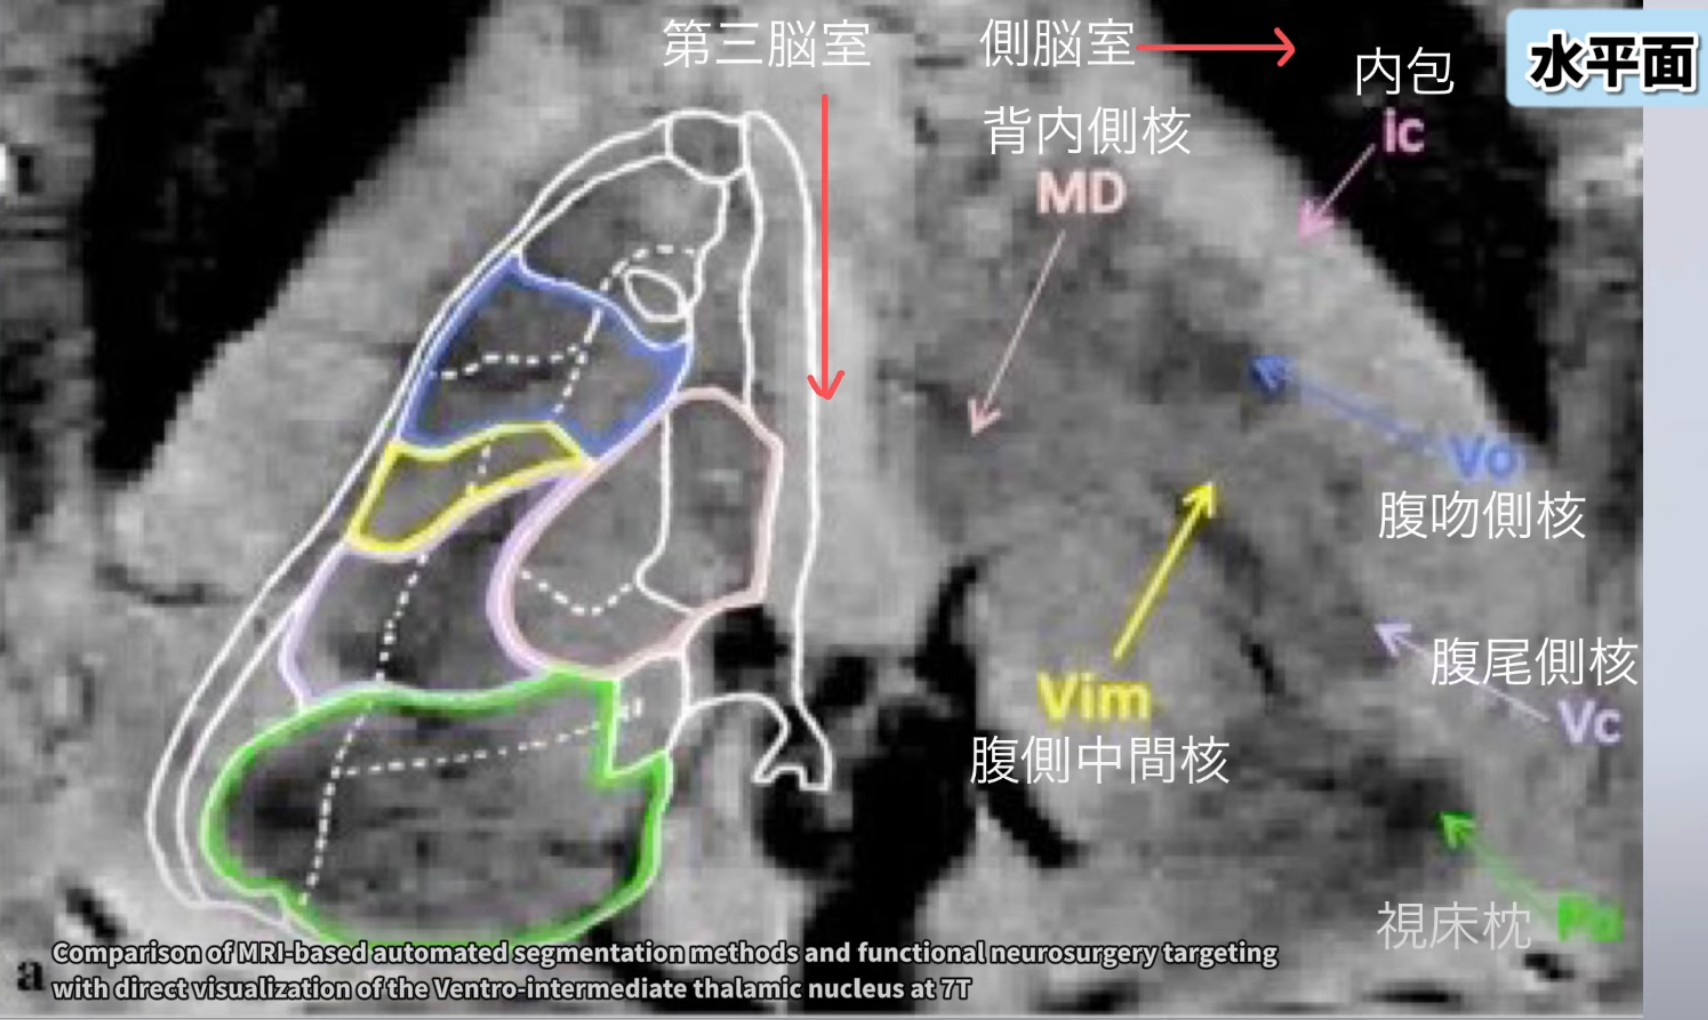

視床背内側核(MD核)とは?

⑧MRI と背内側核: 標準的な MRI で背内側核を視覚化するのはなぜ難しいのですか?また、その接続性と機能についてのより詳しい洞察を提供できる技術は何ですか?

⑧MRI と背内側核: 背内側核は、解像度の制限があるため、標準的な MRI では視覚化することが困難ですが、DTI や fMRI などの高度な技術を使用すると、その接続性と機能についてより多くの洞察を得ることができます。